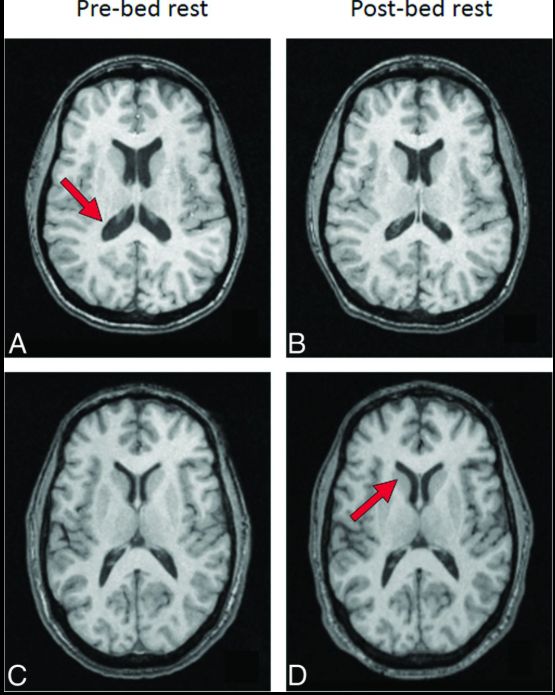

Não bộ của phi hành gia có xu hướng dịch chuyển lên phía trên và ra sau bên trong hộp sọ. (Ảnh: PNAS)

Theo đó, sau thời gian sống và làm việc trên Trạm Không gian Quốc tế (ISS), não bộ của phi hành gia có xu hướng dịch chuyển lên phía trên và ra sau bên trong hộp sọ. Các rãnh não ở vùng đỉnh đầu bị nén lại, trong khi hệ thống khoang chứa dịch não tủy xuất hiện sự thay đổi về hình dạng.

Để có cái nhìn toàn diện, nhóm nghiên cứu đã so sánh ảnh MRI của các phi hành gia với 24 người khỏe mạnh trên Trái Đất. Nhóm đối chứng này được đặt trong tư thế nằm nghiêng đầu xuống đất trong thời gian dài, một phương pháp thường dùng để mô phỏng môi trường vi trọng lực.

Kết quả cho thấy não bộ của nhóm người này cũng xuất hiện sự thay đổi về hình dạng và vị trí, khá giống với những gì quan sát được ở phi hành gia. Tuy nhiên, mức độ dịch chuyển lên trên của não không mạnh bằng, và các cấu trúc não nhìn chung vẫn ổn định hơn so với những người thực sự sống trong không gian.

Não bộ của người thường được đặt trong mô phỏng môi trường vi trọng lực mức độ dịch chuyển lên trên của não không mạnh bằng, và các cấu trúc não nhìn chung vẫn ổn định hơn so với những người thực sự sống trong không gian. (Ảnh: AJNR)